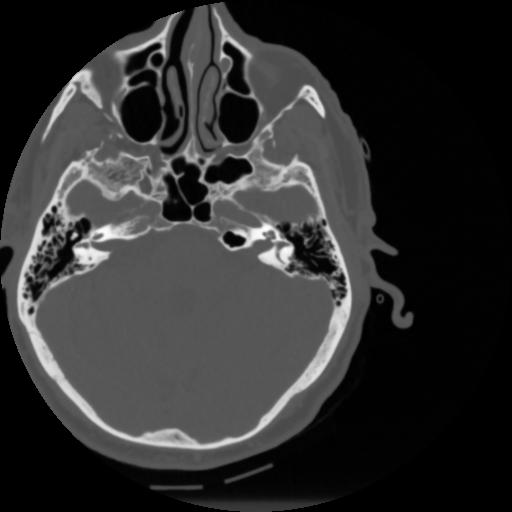

4 CEREBRO,,Vol,0.5,CEREBRO,,